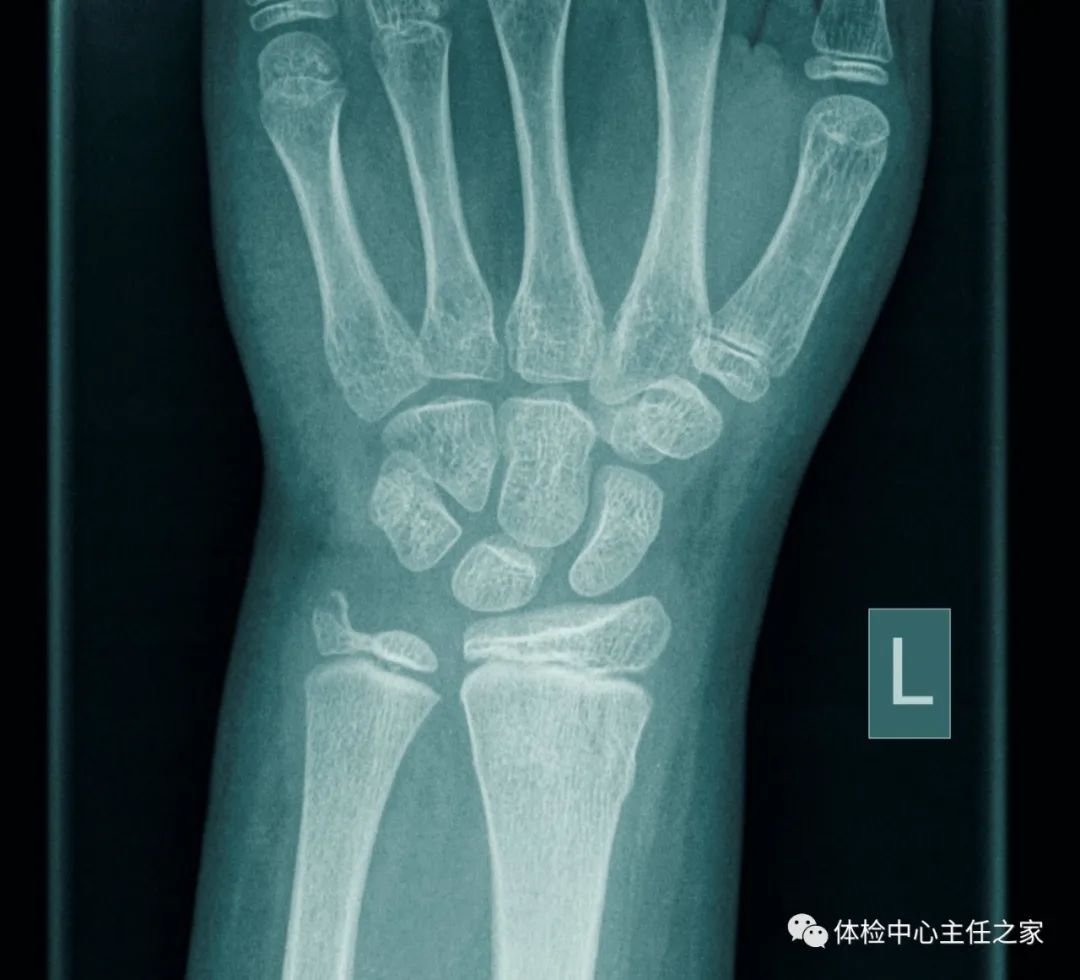

此外,X线是临床骨科的重要检查手段之一。其效果在于检查骨、脊柱和关节等有无器质性病变,明确病变的部位、大小、程度及与周围软组织的关系,为治疗提供参考。而CT可以诊断骨质本身病变、骨折或脱位、骨关节及软组织病变等。

外伤伤及骨头

粗看X线片,细看CT,MRI看不清

各种外伤,如果怀疑伤及骨头,优先选择X光检查,且检查结果快速易得。若要进一步观察,可以选择CT。超声和MRI对于骨皮髓质等看不大清,一般不选择。2